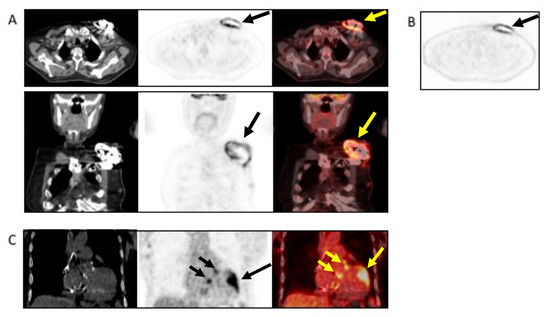

4.4. When to Ask for Nuclear Imaging

5.4. When to Ask for Nuclear Imaging

6.4. When to Ask for Nuclear Imaging

7.3. Role of CCTA in Diagnosing CIED-IE and Local Complications

7.4. When to Ask for Nuclear Imaging

- Chest CT has a specific role in searching for pulmonary embolism, infarct or abscess. The (18F)FDG PET/CT and WBC SPECT/CT have a central role in detecting pocket infection, lead infection, and pulmonary embolism.

- Kestler, M.; Garcia-Pavia, P.; Rodríguez-Créixems, M.; Rotger, A.; Jimenez-Requena, F.; Mari, A.; Orcajo, J.; Hernández, L.; Alonso, J.C.; Bouza, E.; et al. Role of 18F-FDG PET in patients with infectious endocarditis. J. Nucl. Med. 2014, 55, 1093–1098. [Google Scholar] [CrossRef]

- Kouijzer, I.J.; Vos, F.J.; Janssen, M.J.; van Dijk, A.P.; Oyen, W.J.; Bleeker-Rovers, C.P. The value of 18F-FDG PET/CT in diagnosing infectious endocarditis. Eur. J. Nucl. Med. Mol. Imaging 2013, 40, 1102–1107. [Google Scholar] [CrossRef]

- Granados, U.; Fuster, D.; Pericas, J.M.; Llopis, J.L.; Ninot, S.; Quintana, E.; Almela, M.; Pare, C.; Tolosana, J.M.; Falces, C.; et al. Diagnostic accuracy of 18F-FDG PET/CT in infective endocarditis and implantable cardiac electronic device infection: A cross-sectional study. J. Nucl. Med. 2016, 57, 1726–1732. [Google Scholar] [CrossRef]

- Bensimhon, L.; Lavergne, T.; Hugonnet, F.; Mainardi, J.L.; Latremouille, C.; Maunoury, C.; Lepillier, A.; Le Heuzey, J.Y.; Faraggi, M. Whole body [18F]fluorodeoxyglucose positron emission tomography imaging for the diagnosis of pacemaker or implantable cardioverter defibrillator infection: A preliminary prospective study. Clin. Microbiol. Infect. 2011, 17, 836–844. [Google Scholar] [CrossRef]

- Sarrazin, J.-F.; Philippon, F.; Tessier, M.; Guimond, J.; Molin, F.; Champagne, J.; Nault, I.; Blier, L.; Nadeau, M.; Charbonneau, L.; et al. Usefulness of Fluorine-18 positron emission tomography/computed tomography for identification of cardiovascular implantable electronic device infections. J. Am. Coll. Cardiol. 2012, 59, 1616–1625. [Google Scholar] [CrossRef]

- Cautela, J.; Alessandrini, S.; Cammilleri, S.; Giorgi, R.; Richet, H.; Casalta, J.-P.; Habib, G.; Raoult, D.; Mundler, O.; Deharo, J.-C. Diagnostic yield of FDG positron-emission tomography/computed tomography in patients with CEID infection: A pilot study. EP Eur. 2012, 15, 252–257. [Google Scholar] [CrossRef]

- Graziosi, M.; Nanni, C.; Lorenzini, M.; Diemberger, I.; Bonfiglioli, R.; Pasquale, F.; Ziacchi, M.; Biffi, M.; Martignani, C.; Bartoletti, M.; et al. Role of 18F-FDG PET/CT in the diagnosis of infective endocarditis in patients with an implanted cardiac device: A prospective study. Eur. J. Nucl. Med. Mol. Imaging 2014, 41, 1617–1623. [Google Scholar] [CrossRef]

- Tlili, G.; Amraoui, S.; Mesguich, C.; Riviere, A.; Bordachar, P.; Hindié, E.; Bordenave, L. High performances of 18F-fluorodeoxyglucose PET-CT in cardiac implantable device infections: A study of 40 patients. J. Nucl. Cardiol. 2015, 22, 787–798. [Google Scholar] [CrossRef]

- Ahmed, F.Z.; James, J.; Cunnington, C.; Motwani, M.; Fullwood, C.; Hooper, J.; Burns, P.; Qamruddin, A.; Al-Bahrani, G.; Armstrong, I.; et al. Early diagnosis of cardiac implantable electronic device generator pocket infection using 18F-FDG-PET/CT. Eur. Hear. J. Cardiovasc. Imaging 2015, 16, 521–530. [Google Scholar] [CrossRef]